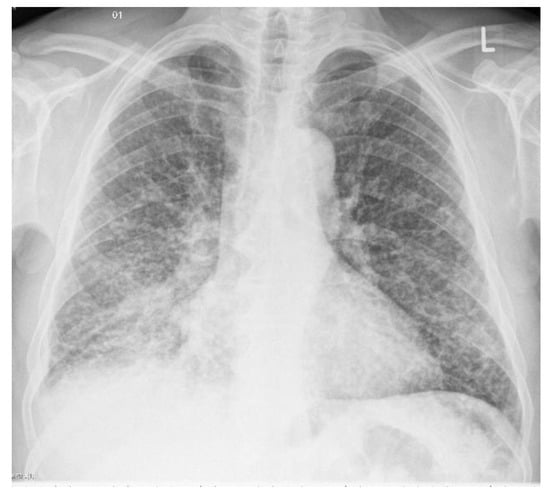

Figure 2.

An example of chest X-ray images showing miliary tuberculosis with pulmonary nodules scattered throughout the lungs uniformly [].

Miliary tuberculosis represents the hematogenous dissemination of an uncontrolled tuberculous infection. Miliary tuberculosis is manifested by an even distribution throughout both the left and right lung lobes. It appears as 1–3 mm diameter nodules, which are uniform in size and uniformly distributed, as depicted in Figure 2. When a tracheal infection is isolated, the consequence is irregular circumferential mural thickening, while broncholiths cause calcified material to enter the lumen. Tuberculous involvement of the pleura usually presents as pleural effusion, empyema, or pleural thickening. Diffuse pleural thickening and adhesions with calcification occur in chronic cases. Patients may show a paradoxical reaction on imaging [,].